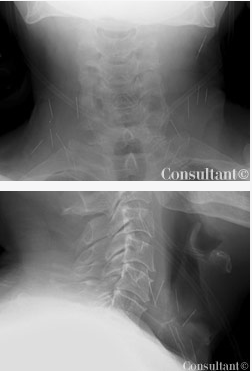

Igor Mamkin, MD, of Farmington, Conn, reports that soft tissue radiographs of the patient's neck revealed at least 17 needles.